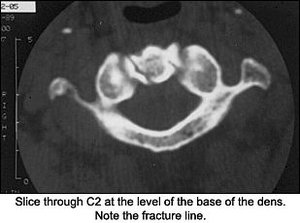

So, what would you do now with this information? Perform orthopedic tests, or would you do further imaging? I decided on more imaging because I'm into radiology. I really didn't want to do any orthopedic tests on the patient because having him run through simple range of motion of the cervical spine aggravated his symptoms, so I ordered a CT of the cervical spine. Upon review of the X-rays, we can now see that the APOM was telling us the answer we couldn't see clearly.

On the CT scan through the C1-2 vertebrae, note the fracture through the dens and the lateral mass of C2. (That was the depression we saw on the APOM of the lateral mass.) Should we look at the APOM view again?

This view above evaluates C1-C2, which cannot be visualized clearly on the lateral. The most important element to check is the alignment of the lateral masses of C1. The intervertebral space should be symmetric. The dens can also be evaluated for fracture in this view, but occasionally overlying shadows may give the false impression of a dens fracture (Mach effect). Correlate the findings with the lateral view of the cervical spine. The incidence of fractures to the axis is about 6 percent, and over 50 percent of those fractures involve some part of the dens.